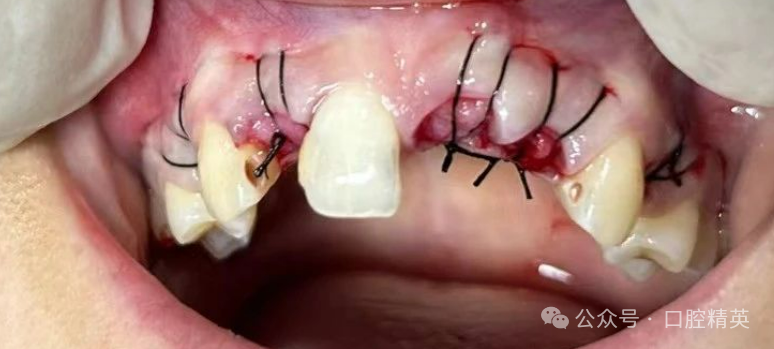

即刻修复技术从美观的角度来看,只要保证患者拔牙位置无异常即可获得良好的近、远中端龈乳头,颊舌向植入角度适宜,且冠部位置和长度均与邻牙相协调,弧度、龈乳头外形更自然逼真,也具有良好的软组织支撑。

近年来人们的生活水平随着社会经济的发展得到了进一步提升,因此人们对种植牙的美观度更为重视,美学效果是患者前牙种植效果的重要指标,红色美学指标中有种植牙的牙龈形态、牙龈轮廓相邻天然牙的龈乳头高度协调一致等问题,其一直以来也是临床医生在前牙修复过程中面对的挑战之一。

同时该指标的影响因素较多,包括拔牙、种植体材料选择、植骨材料选择、基台选择等,并且患者在修复过程中是否采用翻瓣技术也是美学效果的重要因素之一。

传统翻瓣技术的应用,在患者唇侧全厚组织处进行创面关闭,使得角化龈宽度减少,对其牙周健康产生不良影响,同时造成软组织形态与邻牙差异较大,美观度差。

同时传统翻瓣技术还会影响患者口腔的正常血供,不利于后期种植体与周边骨的愈合,进而形成疤痕,造成附着龈丧失,导致种植失败。

与翻瓣技术相比,不翻瓣技术有更好的软组织形态以及牙龈形态,研究发现不翻瓣患者的红色美学指数相比对照组显著更高。

同时不翻瓣技术具有微创特点,不会影响患者的口腔血供,可降低拉拢黏骨膜压迫唇侧骨板的风险,有效保证了软组织的健康,以及保存患者牙槽骨宽度及高度。